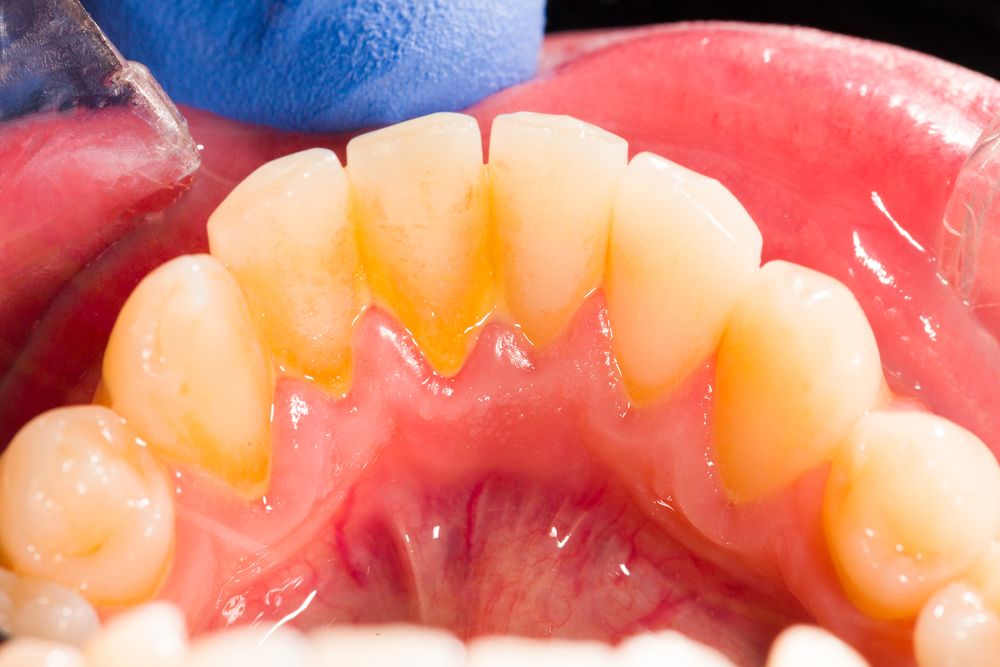

На фотографии зубы с налетом и отложениями из-за неправильной гигиены полости рта.